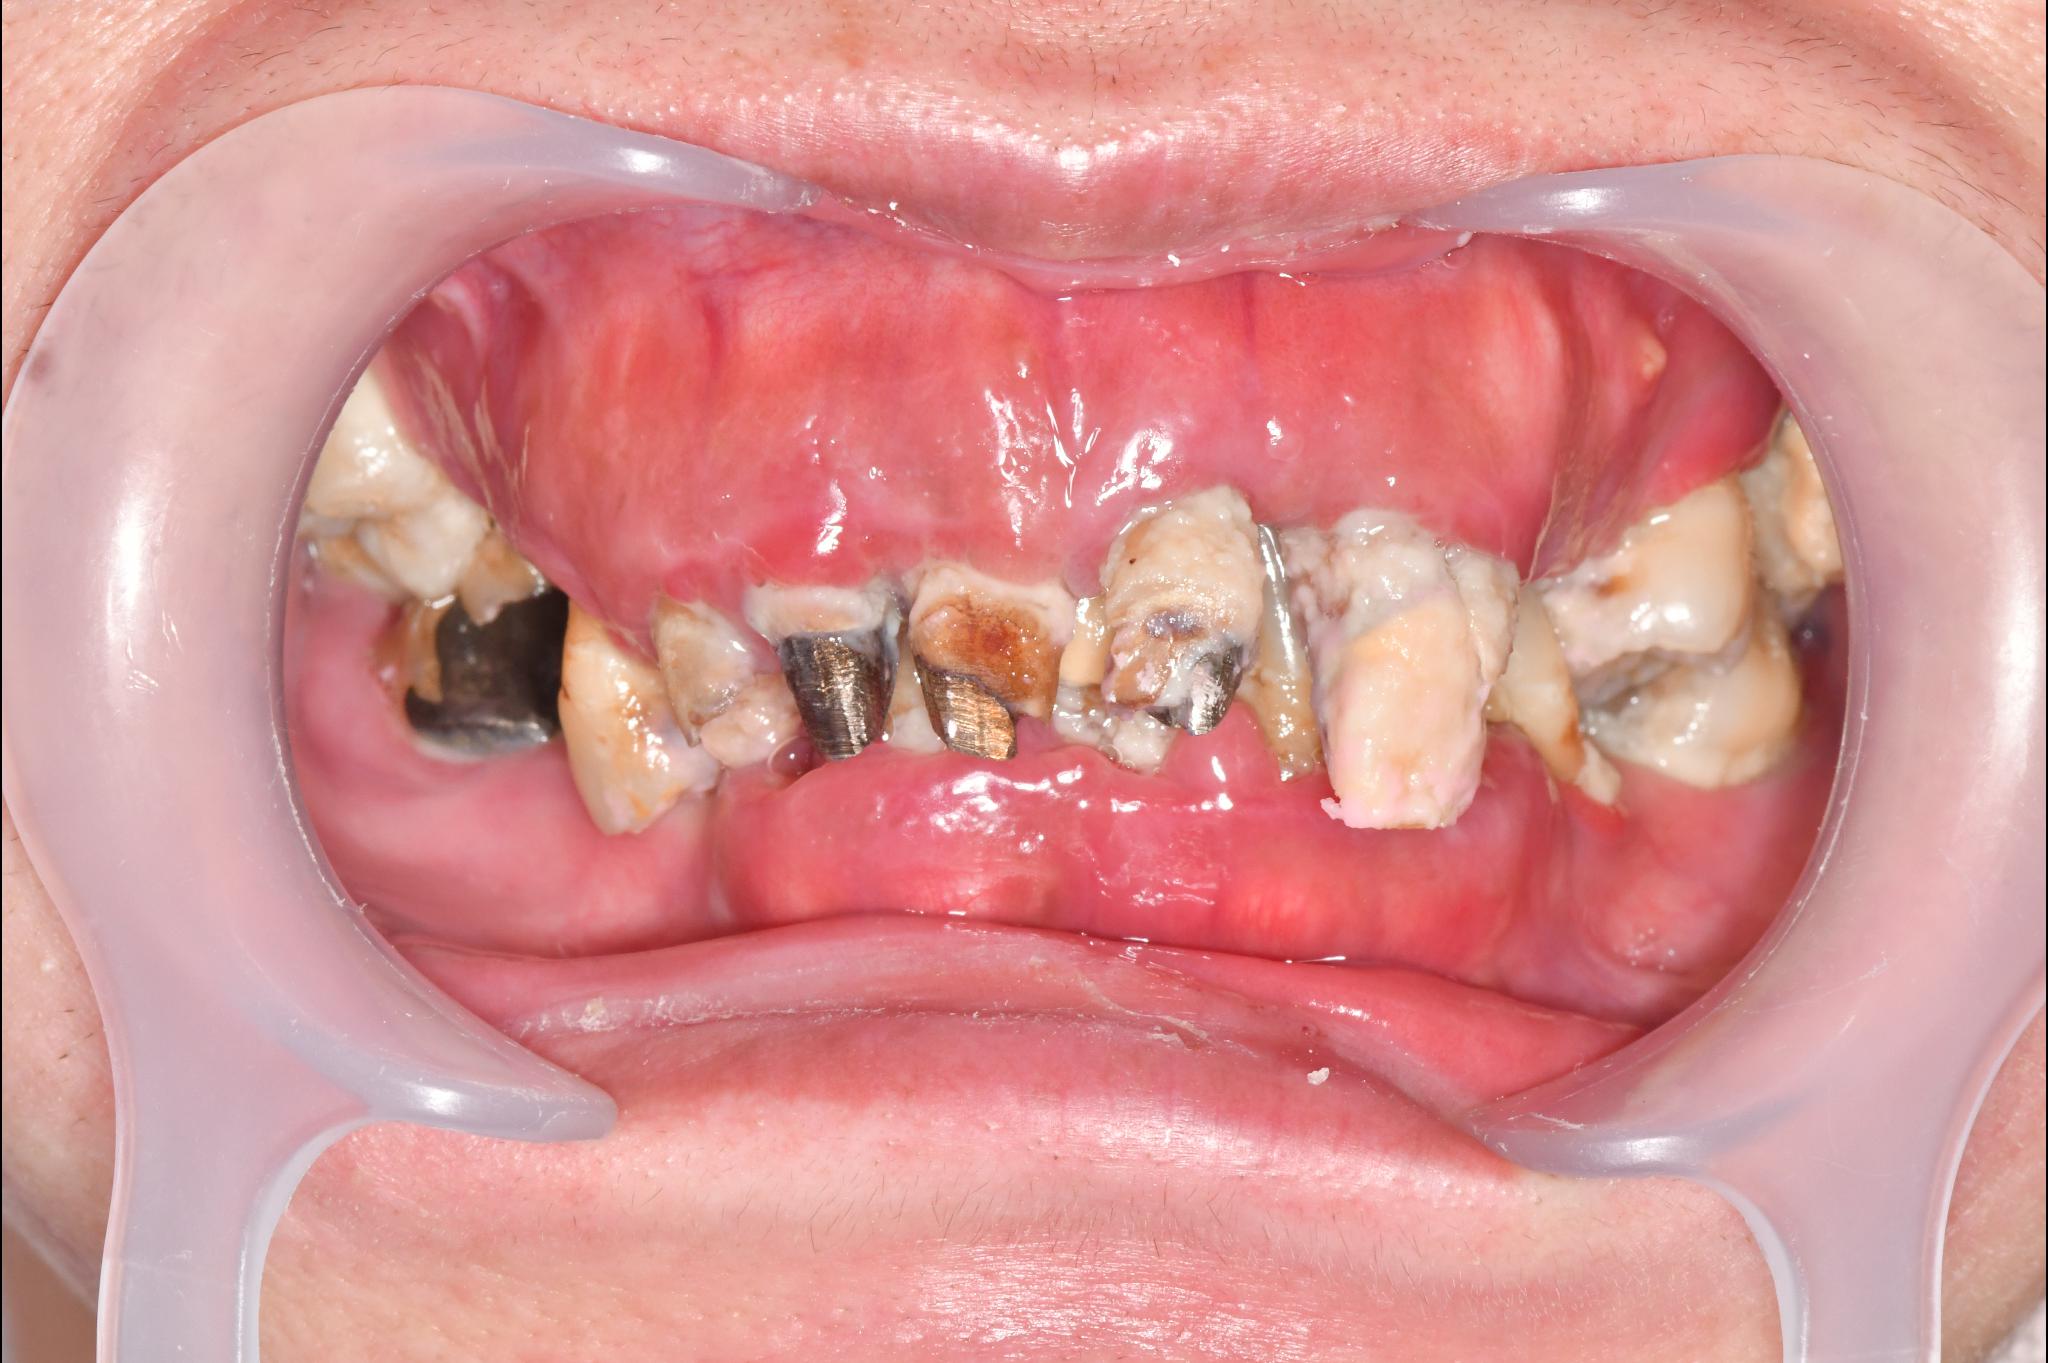

大分県 45歳(女性)

「マスクを外して人付き合いをしたい」

術前

内容 :上下顎オールオン4ザイゴマ0

費用 :4,365,900円

※モニター価格

期間 :半年

リスク:出血・腫れ・痺れ・痛み

「何度も通って恥ずかしい思いを長引かせたくない」という気持ちがありましたので、治療期間が短く、たった1日で固定式の歯が入ることがとても魅力的でした。

手術に対しては強い恐怖心を持っていましたが、実際には術中の記憶はほとんどなく、痛みを感じることもなく無事に終えることができました。

これまでは口元を気にして人との接触を避けていましたが、「笑顔で話したい」という明るい気持ちになれました。